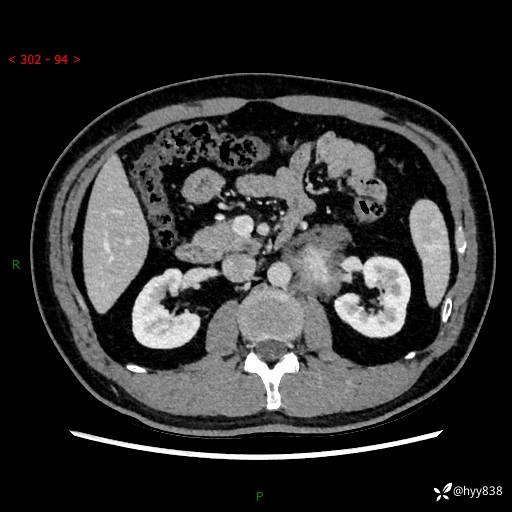

现病史:患者3月余前检查发现左侧腹膜后占位,大小约3.7*4.9cm,平素无腰疼,无肉眼血尿,无尿频尿急等不适,当时未特殊处理,在门诊复查CT提示左侧腹膜后占位,门诊拟“左侧腹膜后占位”收入院。 起病以来,患者精神佳,饮食、睡眠良好,大小便正常,体力体重无明显变化。

腹膜后CT平扫+增强